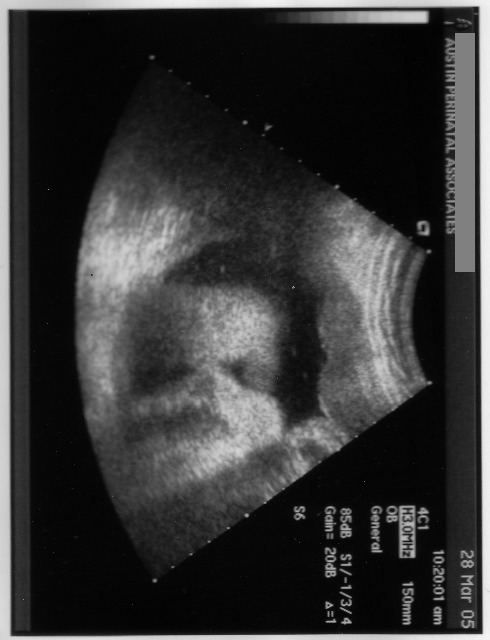

3/28/05